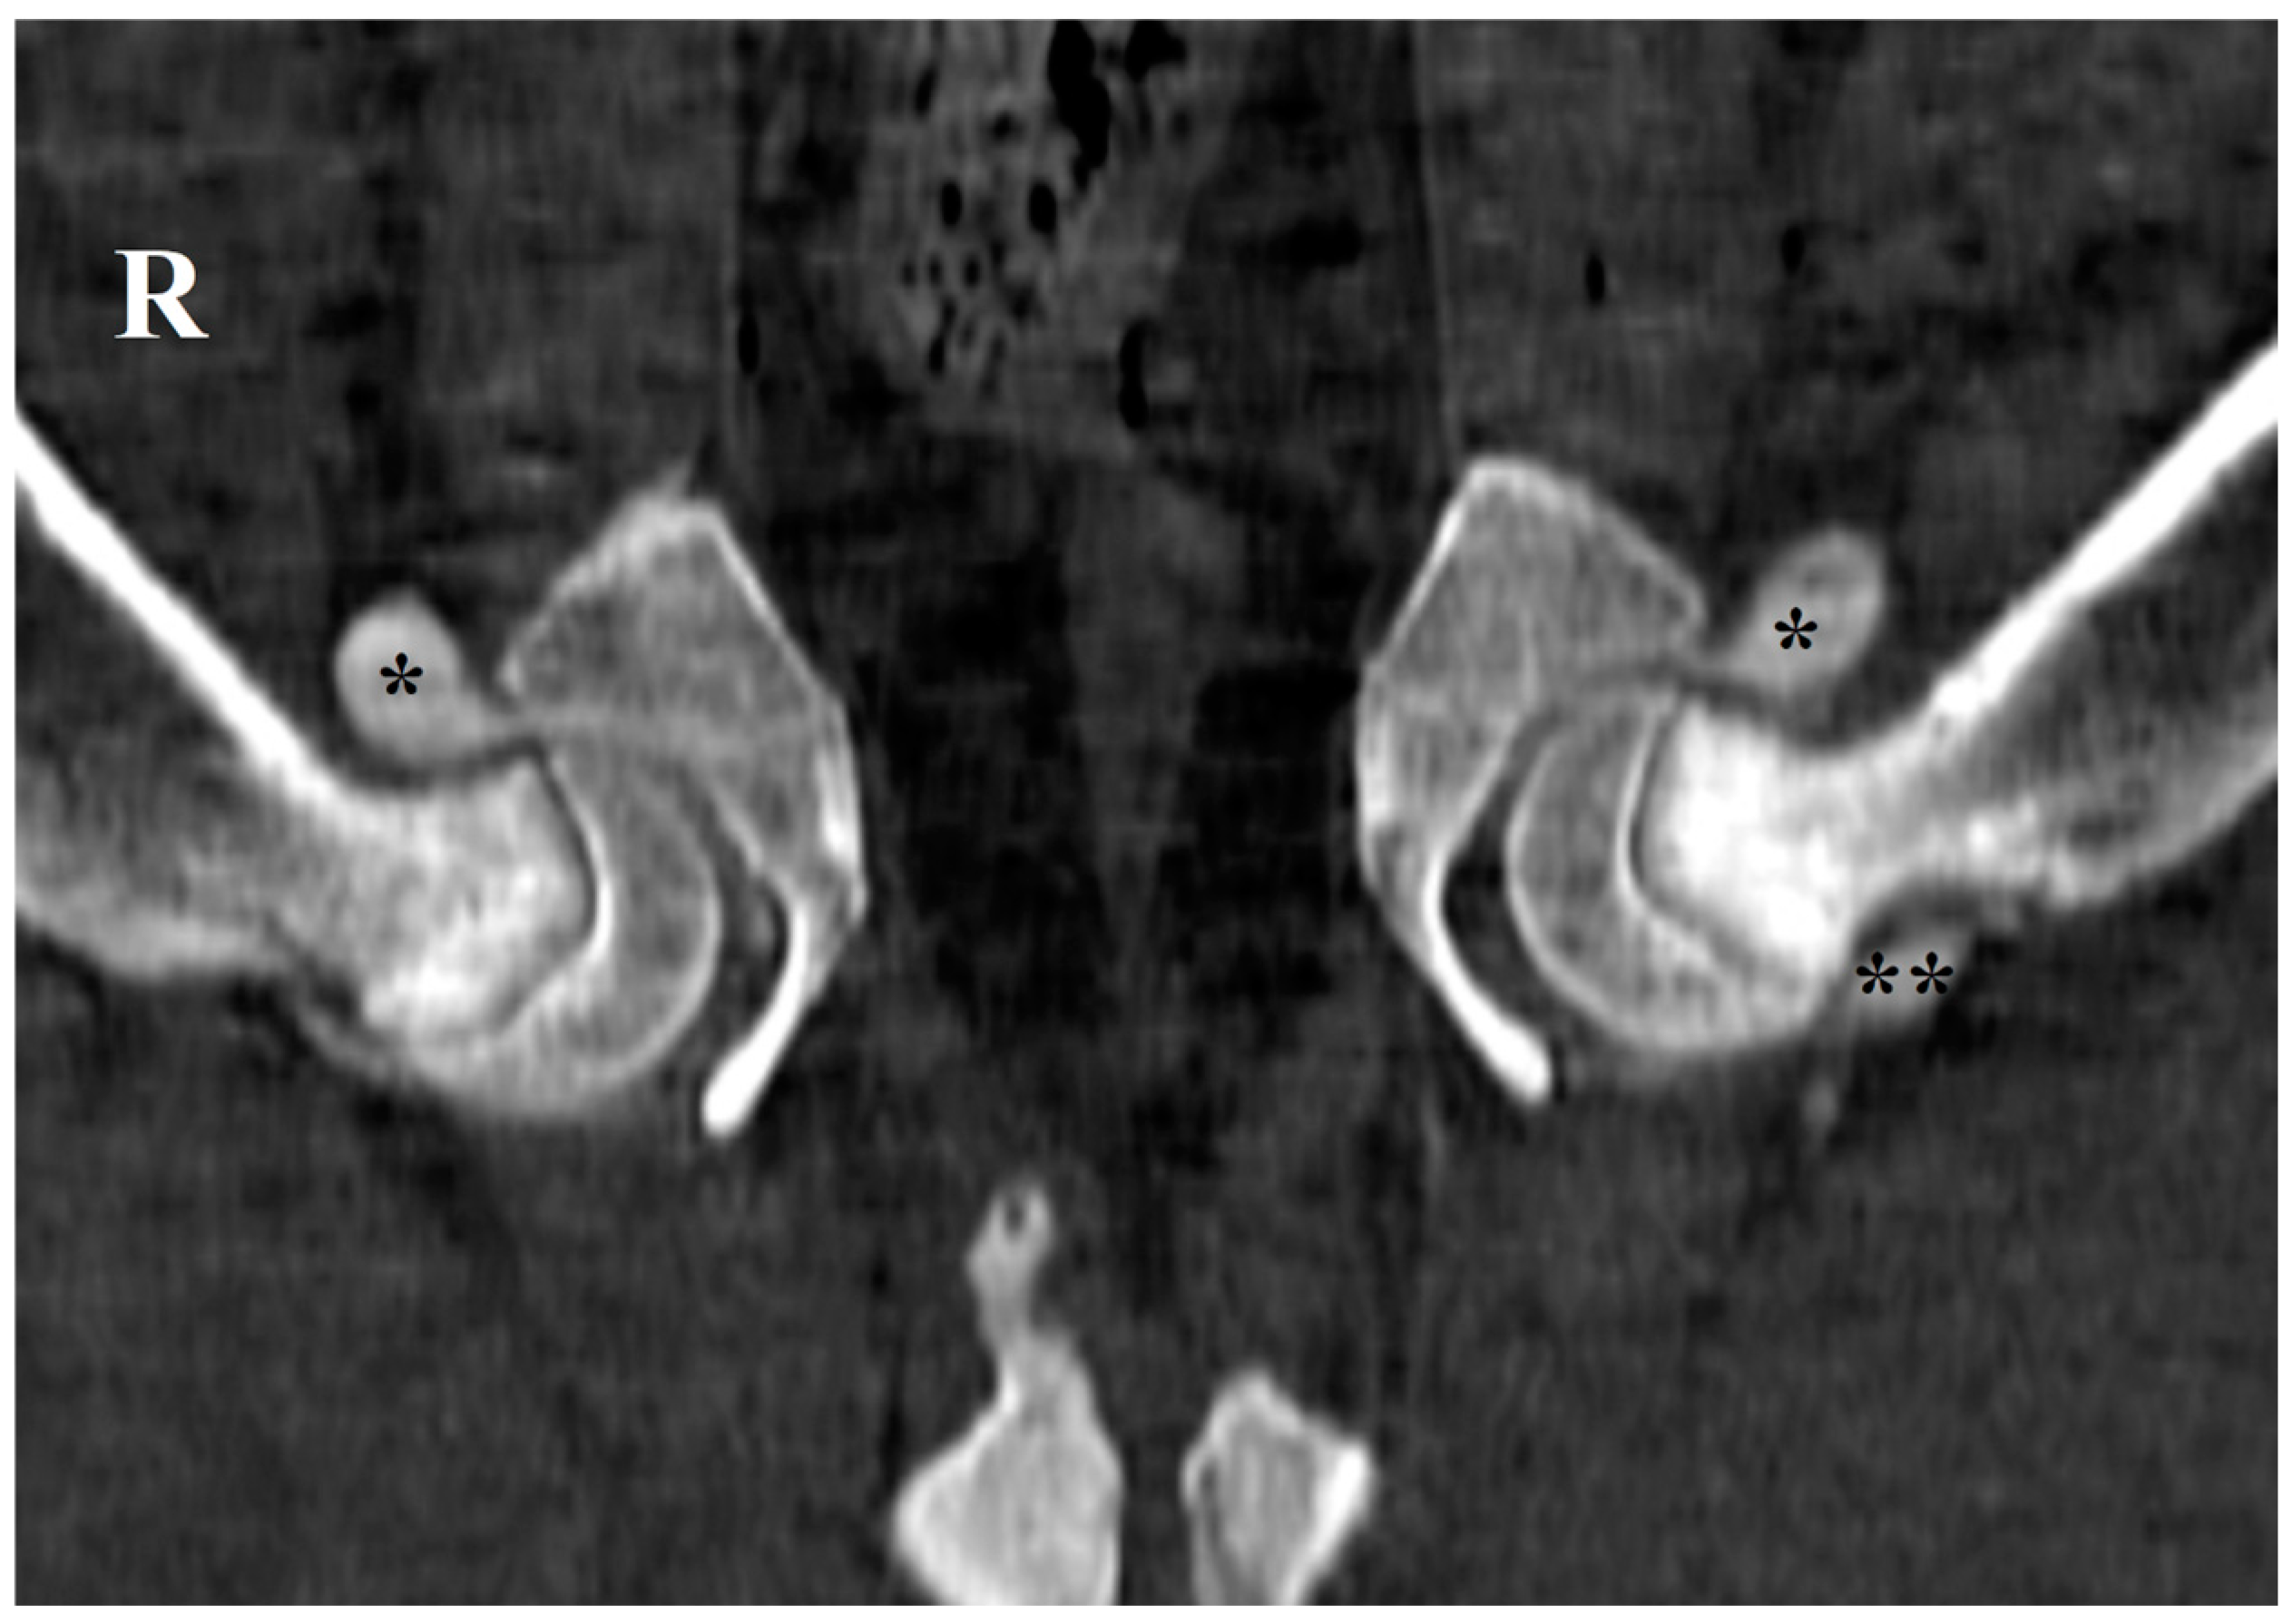

2.3. Ultrasonographic Ventral Hip Joint Approach

- Transverse Femoral Head–Neck Plane